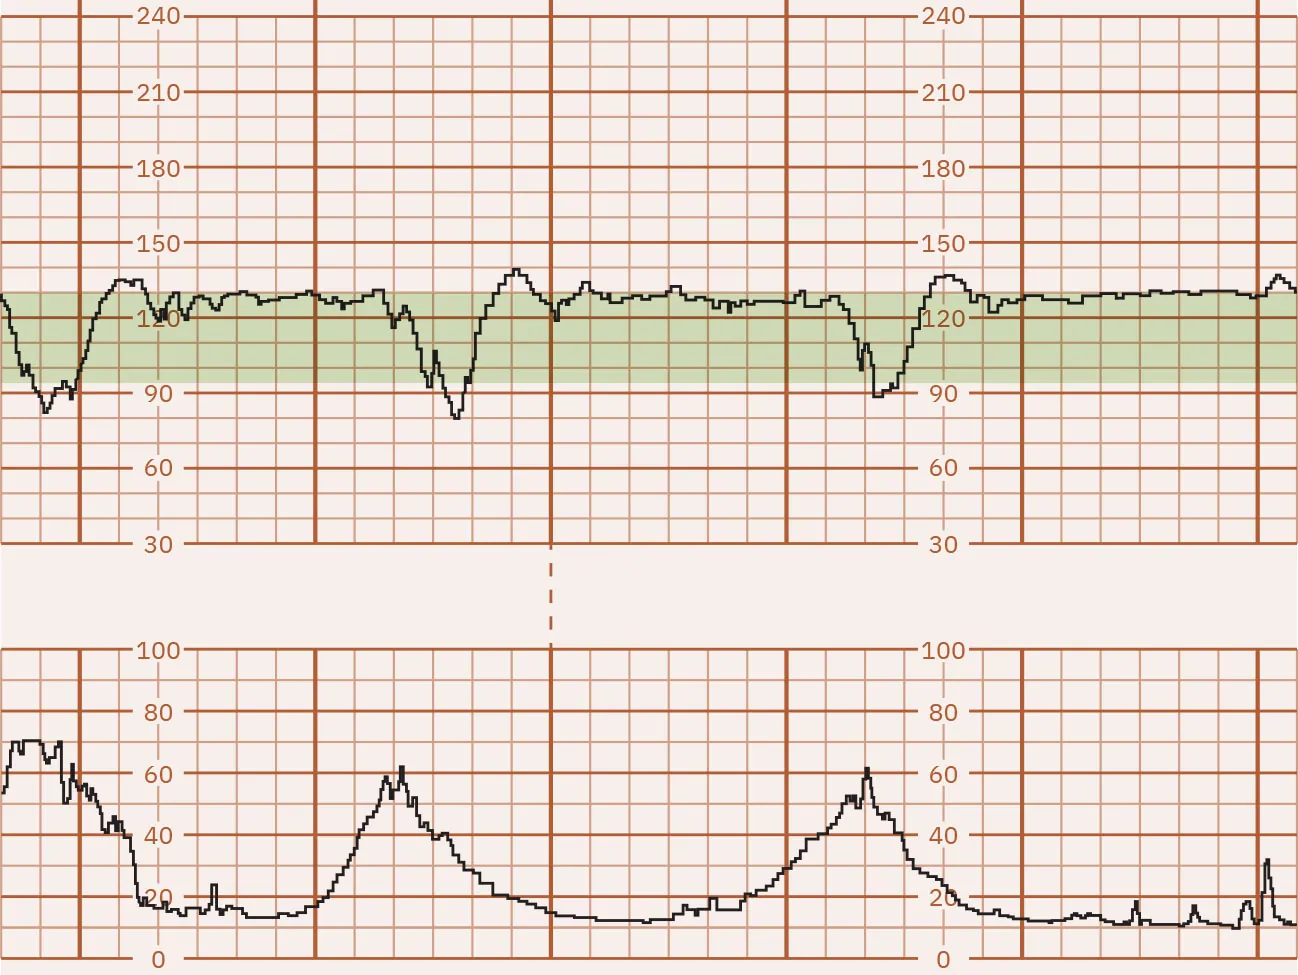

Moderate FHR Variability

Fluctuations between 6 and 25 bpm are considered moderate FHR variability. This is considered normal FHR variability. In most cases, moderate FHR variability is associated with a normal umbilical cord pH. Figure 16.5 shows a monitor tracing that indicates moderate FHR variability.

Fetal heart rate reading indicating moderate variability.

Figure 16.5 Fetal Monitor Tracing: Moderate FHR Variability This fetal monitor tracing shows moderate variability of 6 to 25 bpm. (attribution: Copyright Rice University, OpenStax, under CC BY 4.0 license)